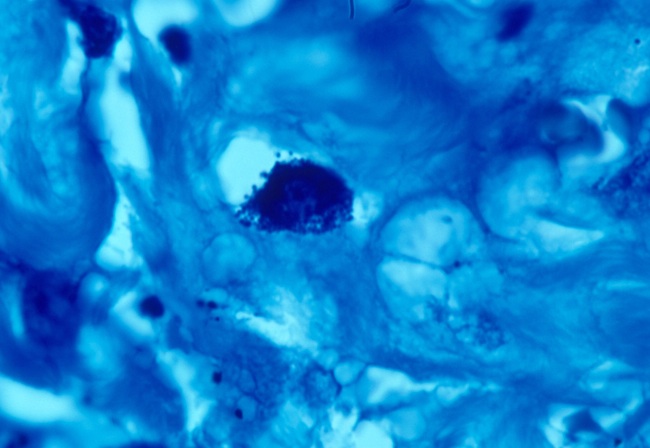

In 1983, a year before the discovery of HIV, I reported variably acid-fast bacteria in AIDS-related KS in two gay men; and also myriads of similar bacteria in an autopsied case of AIDS and KS (Cantwell, 1983). Coccoid forms are numerous in skin tumors of AIDS-related KS (Fig 12).

Fig 12. AIDS-RELATED KAPOSI'S SARCOMA showing tightly-packed intracellular coccoid forms in the dermis of the skin tumor in "star cluster' formation. Fite (acid-fast) stain, x1000